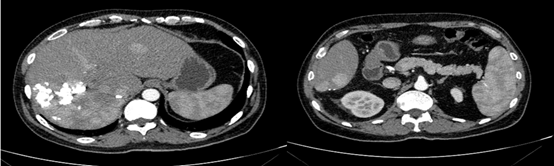

图片

图:第一次TACE治疗

2019年2月21日以碘油5 ml+0.9%氯化钠20 ml+表阿霉素10 mg+雷替曲塞1支稀释后灌注方案行TACE治疗。后复查肝增强CT,未见明显强化,对比2019年1月病灶略缩小,初次TACE治疗达SD。